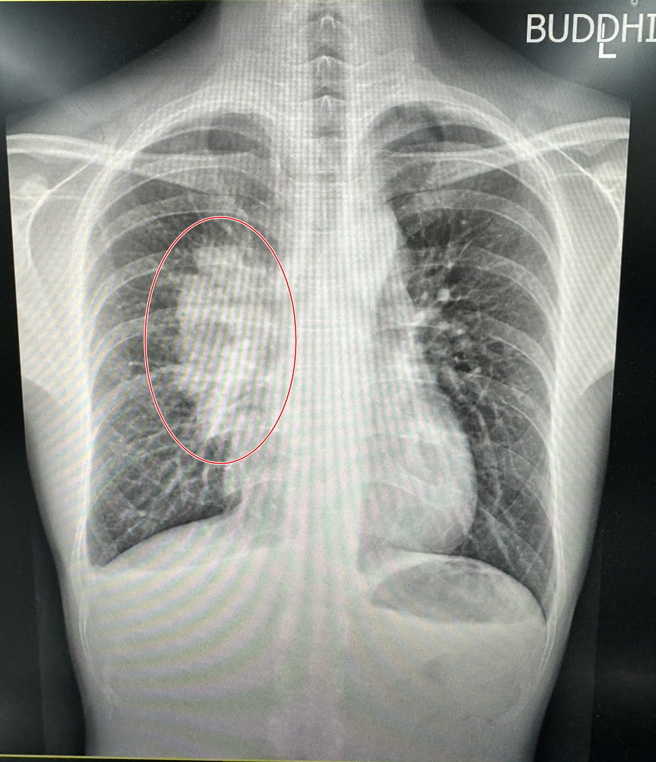

在确定罹癌后,男子接下来被安排做断层扫瞄,发现男子的纵膈腔有一个拳头大般的肿瘤,这就是侯思任在门诊中,所摸到的颈部下硬块,且癌症分期已到第3期,男子马上就被安排做化疗,预计要做12次。